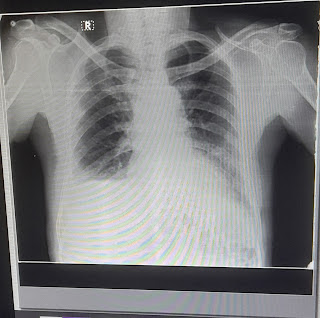

Chest X-ray PA view: